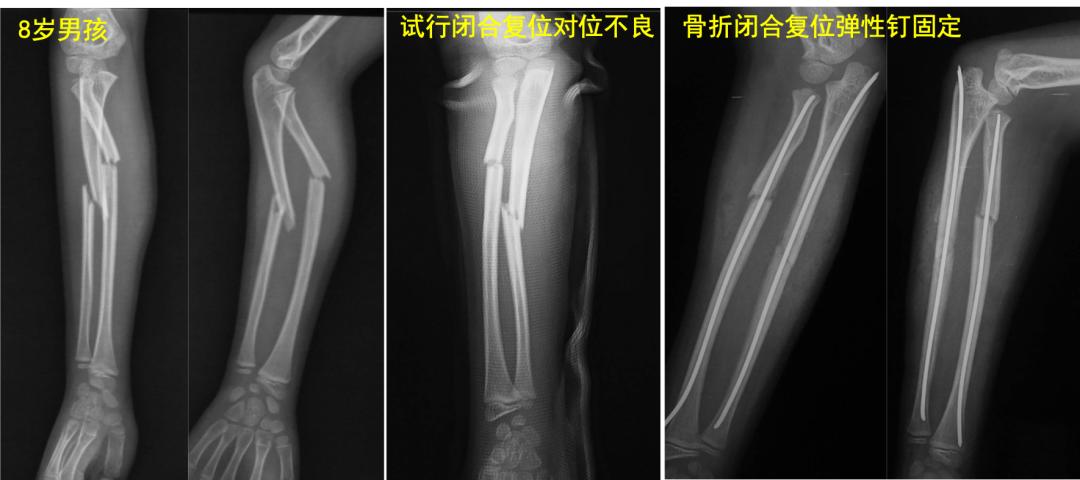

学生:儿童前臂骨折中,哪些是不稳定、保守治疗效果不好的? 老师: P. Schmittenbecher等回顾分析了1143例儿童前臂骨折,97.8%接受保守治疗,随访3-13.5年。结果中或差的比例为13.9与6.9%,有57%需接受二次骨折整复。提出骨折保守治疗疗效不佳与骨折类型密切相关:前臂近1/3骨折、同平面双骨折以及骨折线斜行合并背向成角。对这些儿童前臂骨折,治疗选择时需要警惕。

对于大龄儿童、不稳定型前臂骨折,目前首选骨折闭合复位弹性髓内钉固定。